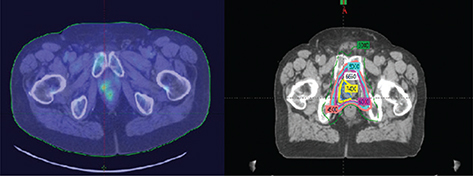

Radiation therapy after prostatectomy remains an important component of patient care. Although surgery remains an important option for patient care in prostate cancer management, often surgeons are confronted with more challenges than anticipated with extracapsular spread of tumor, lymph node involvement, perineural invasion, Gleason grade, and seminal vesicle invasion; all these are indicators of risk for local regional recurrence of disease. Although debate continues as to when to intervene with radiation therapy post-operatively, many in the radiation oncology community feel treatment is more efficacious earlier in the disease process (2326). In contrast, many in the urology community prefer to defer referral of the patient to radiation oncology until there is continuous elevation in PSA (24, 27, 28). Evidence today suggests efficacy with earlier intervention than later before PSA becomes significantly elevated. Having established this point, the radiation oncology community is challenged by defining a target to treat as treatment is being directed to a biomarker. Radiation oncologists have traditionally targeted the urethral anastomosis, former prostate capsule, and the undersurface of the bladder as high-risk targets with nodal volume therapy treated at the discretion of the radiation oncologist on an individual basis driven by the initial pathology. Although this demonstrated success, the choice of targets was thoughtful but simultaneously arbitrary based on the perception of tissues considered at risk (2931). Modern imaging has helped radiation oncologists pivot from this position and re-visit target definitions by optimizing targets that would be considered high risk and targets of intermediate risk with the option of dose painting to high-risk targets (Figure 3). In this case, metabolic imaging supported the identification of a bulk tumor aggregate which could be treated as a high-risk target with adjoining tissue, and tissue previously defined as high risk defined at intermediate risk, thus limiting the risk of normal tissue injury. The high dose volumes were titrated to areas of activity defined on anatomical imaging.

Fig 3

Figure 3. PET imaging. (left) PET scan image of recurrent disease in a post-prostatectomy patient and the radiation therapy treatment plan (right) directed to tissues considered of high risk (PET avid) and intermediate risk (28). Image courtesy of the Department of Radiation Oncology, UMass Chan Medical School and UMass Memorial Health.